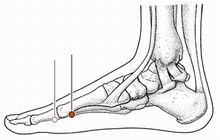

解溪穴

经穴名。出《灵枢·本输》。别名草鞋带。属足阳明胃经。经(火)穴。在足背与小腿交界处的横纹中央凹陷中,当拇长伸肌腱与趾长伸肌腱之间。布有腓浅神经,腓深神经和胫前动、静脉。主治头痛,眩晕,目赤,腹胀,便秘,癫狂,头面浮肿,下肢痿痹,脚腕无力等。直刺0.3-0.5寸。艾条灸5-10分钟。

至阴

经穴名。出《灵枢•本输》。属足太阳膀胱经。井(金)穴。在足小趾末节外侧,距趾甲角0.1寸。布有趾底固有神经,足背外侧皮神经及趾背动脉及趾底固有动脉形成的动脉网。主治头痛,昏厥,鼻塞,目翳,鼽(鼻丑),滞产,胞衣不下,及胎位不正等。针刺0.1-0.2寸,或点刺出血。艾炷灸3-7壮;或艾条灸10-15分钟。